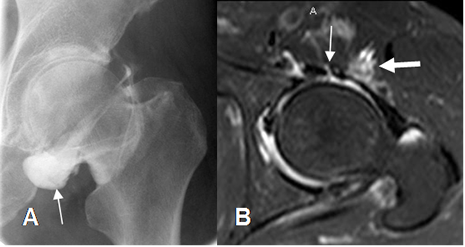

Fig 113. Ruptura del labrum.

A: Rx AP. Signos de pinzamiento tipo pincer.

B: ArtroRM coronal en STIR. Defecto del labrum superior, por ruptura. (Flecha gruesa).

Fig 114. Ruptura del labrum.

B: ArtroRM axial en STIR. Defecto del labrum posterior, por ruptura.